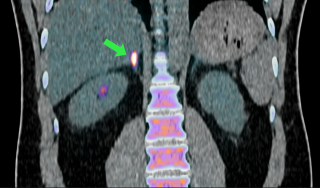

uses a radioactive tracer detected by the Pet-scan. It helps locate adrenal areas that produce too much aldosterone.

The first uses of the scanner made it possible to precisely locate areas of overproduction in 17 patients, without any side effects. Professor Bryan Williams, chair of the Department of Medicine at UCL and leader of the study, summarizes the visual impact of the technique.

“This is the first time we can visualize this disease. You can see it light up on the scan. The intensity of the signal reflects the level of aldosterone overproduction. This could allow us, in the future, to target these overproducing areas more precisely.”

Imaging showing hyperaldosteronemia